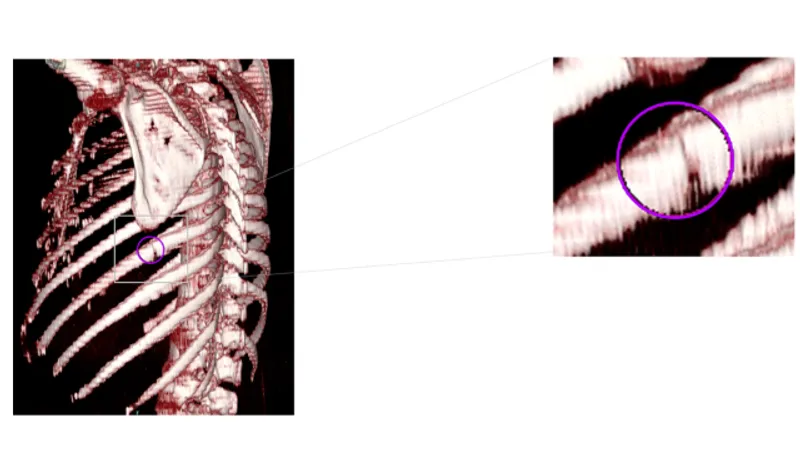

胸部CT画像から肋骨骨折の候補を検出して表示する機能です。医師が再確認することで見落しを低減します。

本プログラムは、胸部CT画像をオンプレ/クラウド環境にて自動解析し、肋骨骨折が疑われる箇所を検出してマーキングするソフトウェアです。

CT画像から三次元解析する当社技術を活用することで、骨表面を構成する皮質骨の断裂が認められる箇所を肋骨骨折の候補として検出します。また、SYNAPSE SAI viewer*1に搭載されている、医師が骨折の場所などを指し示す際に引用する「骨番号」を自動付与する「ラベリング機能*2」を併用でき、所見文を作成する際の負荷を軽減します。さらに、二次元画像から三次元画像を構成して観察できる 「VR機能」と併用すると、どの方向から外傷を受けたのかなど、骨折の原因分析に活用できる三次元的な情報を確認することができます。 *1 SYNAPSE SAI viewer用 画像表示プログラム 販売名:画像診断ワークステーション用プログラム FS-V686型 認証番号:231ABBZX00028000 *2SYNAPSE SAI viewer用 画像処理プログラム 販売名:画像診断処理プログラム FS-AI683型 認証番号:231ABBZX00029000